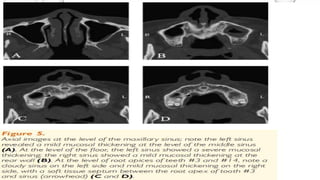

Case 1

CASE 2

• A CASE REPORT BY MICHAEL A. BRUNSVOLD SAID THAT MAXILLARY SINUSITIS

MAY DEVELOP FROM THE EXTENSION OF PERIODONTAL DISEASE. IN THIS CASE,

RECONSTRUCTED THREE-DIMENSIONAL IMAGES FROM MULTIDETECTOR SPIRAL

COMPUTED TOMOGRAPHS WERE HELPFUL IN EVALUATING PERIODONTAL BONY

DEFECTS AND THEIR RELATIONSHIP WITH THE MAXILLARY SINUS.

• A 42-YEAR-OLD WOMAN IN GOOD GENERAL HEALTH PRESENTED WITH A

CHRONIC DEEP PERIODONTAL POCKET ON THE PALATAL AND

INTERPROXIMAL ASPECTS OF TOOTH #3 AND #14. PROBING DEPTHS OF THE

TOOTH RANGED FROM 2 TO 9 MM, AND IT EXHIBIT A CLASS 1 MOBILITY.

RADIOGRAPHS REVEALED A CLOSE RELATIONSHIP BETWEEN THE ROOT APEX

AND THE MAXILLARY SINUS. THE PATIENT’S PERIODONTAL DIAGNOSIS WAS

LOCALIZED SEVERE CHRONIC PERIODONTITIS. TREATMENT OF THE TOOTH

CONSISTED OF CAUSE-RELATED THERAPY, SURGICAL EXPLORATION, AND

BONE GRAFTING. A VERY DEEP CIRCUMFERENTIAL BONY DEFECT AT THE

PALATAL ROOT OF TOOTH #14 WAS NOTED DURING SURGERY. AFTER THE

OPERATION, THE WOUND HEALED WITHOUT INCIDENCE, BUT 10 DAYS

LATER, A MAXILLARY SINUSITIS AND PERIAPICAL ABSCESS DEVELOPED. TO

CONTROL THE INFECTION, AN EVALUATION OF SINUS AND ALVEOLUS USING

COMPUTED TOMOGRAPHS WAS PERFORMED, SYSTEMIC ANTIBIOTICS WERE

PRESCRIBED, AND ENDODONTIC TREATMENT WAS INITIATED.

• RESULTS: TWO WEEKS AFTER SURGICAL TREATMENT, THE INFECTION WAS

RELIEVED WITH THE HELP OF ANTIBIOTICS AND ENDODONTIC TREATMENT.

BILATERAL BONY COMMUNICATIONS BETWEEN THE MAXILLARY SINUS AND

PERIODONTAL BONY DEFECT OF MAXILLARY FIRST MOLARS WERE SHOWN ON

THREE-DIMENSIONAL COMPUTED TOMOGRAPHS. THE DIGITALLY

RECONSTRUCTED IMAGES ADDED VALUABLE INFORMATION FOR EVALUATING

THE PERIODONTAL DEFECTS. THREE-DIMENSIONAL IMAGES FROM SPIRAL

COMPUTED TOMOGRAPHS (CT) AIDED IN EVALUATING AND TREATING THE

CLOSE RELATIONSHIP BETWEEN MAXILLARY SINUS DISEASE AND ADJACENT

PERIODONTAL DEFECTS.